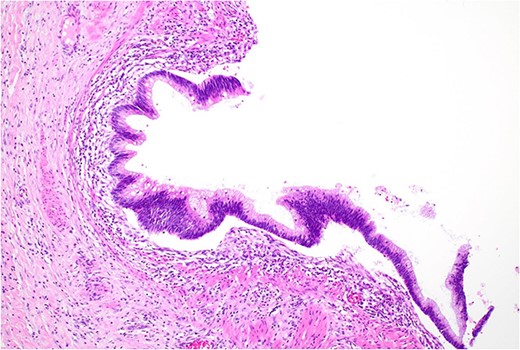

Histopathology macroscopically identified a 42-mm cystic caecal mass adjacent to the ileocaecal valve (Figs 4–5). Microscopic examination revealed a duplication cyst involving the ileal and colonic tissue comprised of a complete duplication of the colonic wall including mucosa, submucosa and muscularis propria, which was shared with the involved colon (Fig. 6). There was no mucosal connection to adjacent normal bowel. There was some ulceration with inflammatory changes in the overlying mucosa suggestive of prior cyst perforation and areas of attenuated villiform mucinous epithelium with features of low grade dysplasia (Figs 7-8). Special stains for organisms (Periodic Acid-Schiff (PAS), Fredericamycin A (FMA), Ziehl-Neelsen (ZN) and modified ZN) were negative. There were no granulomas, heterotopic mucosa or evidence of malignancy. Twenty-nine lymph nodes were identified with no evidence of malignancy.

Area of dysplastic mucosa (right) within the duplication cyst that shares a common wall with the right colon (left), low power.